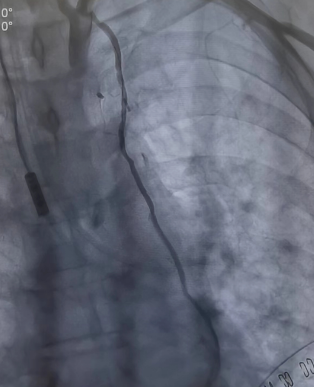

將兩者結(jié)合的手術(shù)方式就是雜交技術(shù)即“一站式微創(chuàng)”手術(shù)。手術(shù)先在左側(cè)胸壁做一個(gè)5-7厘米切口,進(jìn)行左胸廓內(nèi)動(dòng)脈-左前降支(LIMA-LDA)架橋。接著進(jìn)行冠脈造影,檢查L(zhǎng)IMA-LDA橋血管通暢度。同時(shí)在冠脈其他狹窄部位放入冠脈支架。

同期進(jìn)行冠脈放支架(檢查L(zhǎng)IMA橋血管通暢)